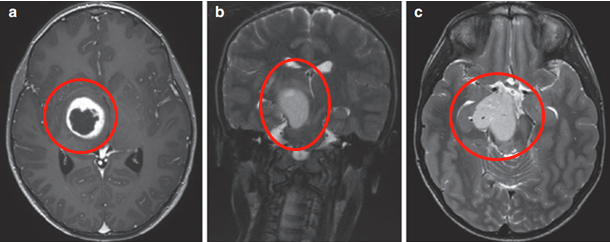

3歲患兒因嘔吐和巨腦畸形就醫(yī)。CT及MRI顯示右側(cè)丘腦病變伴鈣化及后三腦室梗阻,引起腦積水(圖1)。

丘腦膠質(zhì)瘤

圖1

在8歲、11歲和13歲時(shí),James T. Rutka教授成功地利用三腦室內(nèi)窺鏡切開術(shù)治療腦積水(圖2為系列影像),且影像顯示腫瘤增大和多發(fā)腫瘤囊腫(箭頭狀),并逐漸出現(xiàn)左上肢震顫。

圖2

患兒在13歲時(shí)進(jìn)行了神經(jīng)導(dǎo)航和超聲引導(dǎo)下的活檢,證實(shí)為腦瘤為WHO I級(jí),毛細(xì)胞星形細(xì)胞瘤。

腫瘤囊腫持續(xù)擴(kuò)大(圖3),患兒發(fā)展為急性偏癱。

圖3

示同側(cè)內(nèi)囊(負(fù)責(zé)人體肢體運(yùn)動(dòng))前外側(cè)移位(箭頭)(圖4)。超聲引導(dǎo)下將Ommaya導(dǎo)管和儲(chǔ)層插入腫瘤囊腫。

圖4

術(shù)后MRI顯示囊腫和導(dǎo)管頭端減壓(箭頭)。(圖5j)四個(gè)月后,由于患兒的偏癱沒有好轉(zhuǎn),Rutka教授為其行經(jīng)胼胝體半球間入路及腫瘤次全切除術(shù)。

術(shù)后影像(圖5),術(shù)后患兒偏癱好轉(zhuǎn),患兒生長(zhǎng)和智力發(fā)育正常,近期隨訪顯示腦瘤未復(fù)發(fā)。免疫組化檢測(cè)RAF V600E突變免疫無陽性,H3K27M陰性。

圖5